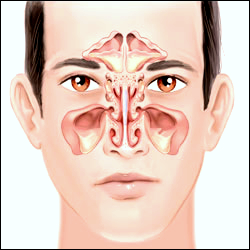

Concha Bullosa

Conchae are structures made of bone inside of your nose. They help control the airflow into your nose, besides cleaning and warming air that is inhaled so that it’s ready for respiration.

Concha bullosa happens when one of the conchae, or turbinates, inside your nose becomes filled with a pocket of air. This is also known as pneumatization of the turbinate.

There are three pairs of conchae in your nose on either side of the septum. Your septum is the structure that divides your nose in half.

These conchae include:

- The superior turbinates, which are the highest conchae in your nose, near your brain. These protect the olfactory bulb, the part of your brain that helps you smell.

- The middle turbinates, which sit between the superior and inferior conchae. They help keep inhaled air from going directly into your sinuses.

- The inferior turbinates, which are the lowest conchae in your nose. They help moisturize and warm up inhaled air before it goes into your lungs.